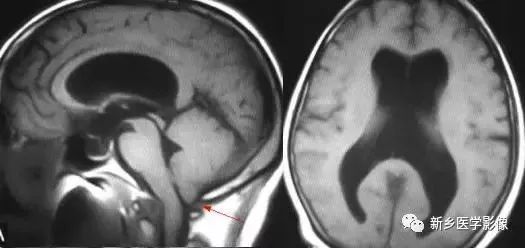

❽ 胼胝体发育不良

胼胝体发育不良可单独发病,但更常见的是伴有中枢伸经系统的其他畸形,包括胼胝体周围脂肪瘤、脑膨出、交通性脑积水、Chaiar-II畸形、Dandy-Walker囊肿、脑裂畸形等。

临床上可无症状或仅有轻度临床症状,临床检查可见眼距过宽、大头畸形、智力发育迟滞等。

胼胝体缺失时,MR冠状位上侧脑室前角呈新月形表现,侧脑室体部分离,呈垂直状平行走行。